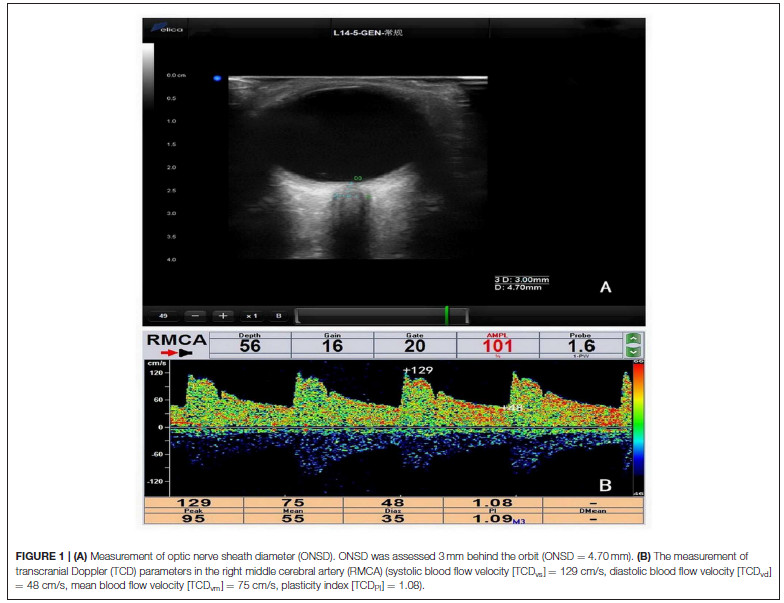

Background/Aims: Non-invasive measurement of intracranial pressure (ICP) usingultrasound has garnered increasing attention. This study aimed to compare the reliability of ultrasonographic measurement of optic nerve sheath diameter (ONSD) and transcranial Doppler (TCD) in detecting potential ICP elevations.

【Delica MVU-6300 (Shenzhen, Guangdong, China) was used to obtain both TCD and ONSD measurements】

Methods: Patients who needed lumbar puncture (LP) in the Department of Neurology were recruited from December 2016 to July 2017. The ONSD and TCD measurements were completed before LP.

Results: One hundred sixty-five participants (mean age, 41.96 ± 14.64 years; 80 men; 29 patients with elevated ICP) were included in this study. The mean ICP was 170 ± 52 mmH2O (range, 75–400 mmH2O). Univariate analyses revealed that ICP was non-significantly associated with TCD parameters and significantly associated with ONSD (r = 0.60, P < 0.001). The mean ONSD of the elevated ICP group was significantly higher than that of the normal ICP group (4.53 ± 0.40mm vs. 3.97 ± 0.23mm; P < 0.001). Multivariate linear regression determined that the difference between ICP and ONSD is significant.

Conclusions: In the early stage of intracranial hypertension, ONSD is more reliable for evaluating ICP than TCD.